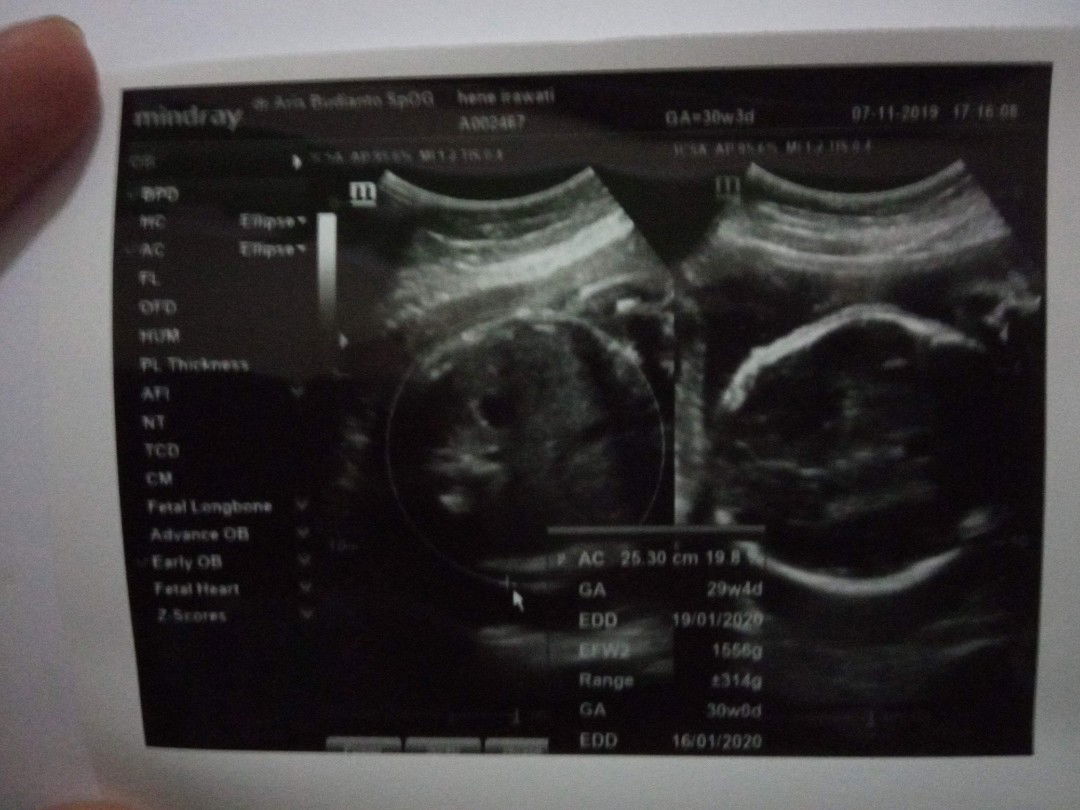

bbj janin kurang

Bund.. Share tips naikin bbj dong Ceritanya aku ini dari awal hamil sampe 34week hanya naik 7kg dan perut memang agak kecil, sempat khawatir dan ternyata kekhawatiranku benar, bbj ku kurang, 4 minggu lalu tanggal 7 november 30week bbj 1,5kg dan 5 desember 32week 1,9kg padahal harusnya sekarang 34week knpa di hasil usg 32week ya? Kata dokter perlu 600gram lagi sampe lahiran buat bbjnya normal 2,5kg